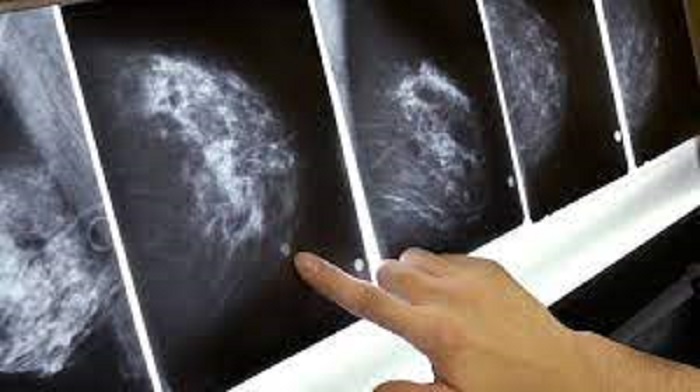

Durante sessão plenária, nesta quarta-feira (6), foi aprovado o Projeto de Lei 340/2021, que institui as diretrizes para o Programa de Exame de Mamografia Móvel no Maranhão.

De acordo com o PL, de autoria do deputado Ciro Neto (PP), o objetivo é articular ações que visem ao aumento da cobertura desse exame em todo o estado e desenvolver ações coordenadas para garantir o fornecimento regular de mamografia às mulheres na faixa etária indicada para o rastreamento do câncer de mama, a cada dois anos.

O programa contemplará, prioritariamente, as mulheres entre 50 e 69 anos de idade, nos municípios maranhenses que se encontrarem com os menores percentuais de realização de exames de mamografia, segundo o Índice de Desempenho do Sistema Único de Saúde (IDSUS).